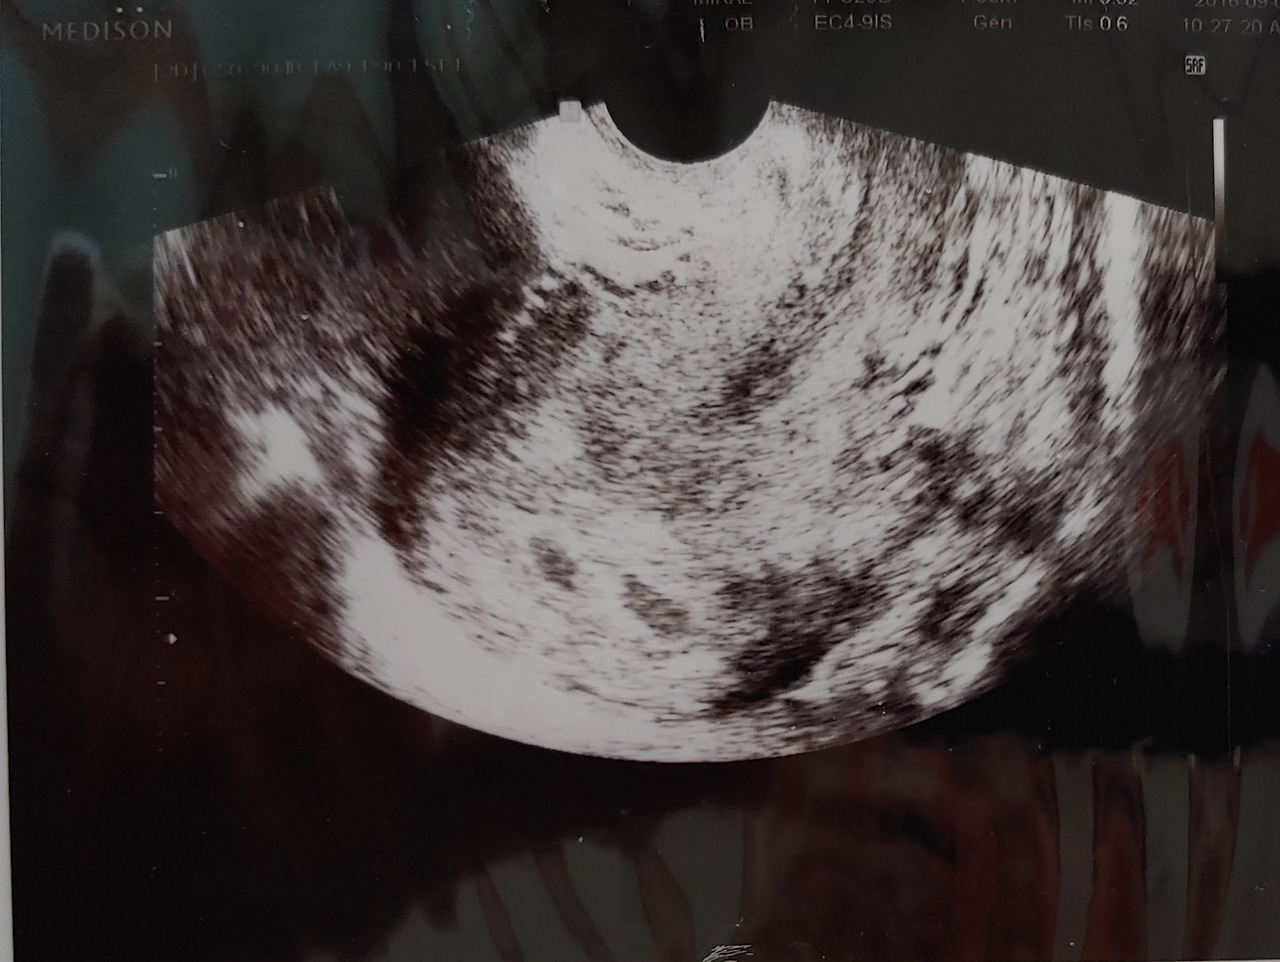

지난번 계류 유산 때 아기집 확인에 실패한 경험이 있기 때문에 이번에 아기집을 보는 것은 나에게 매우 중요한 일이었다. 두 번째 피검사 날, 그러니까 임신 5주 차가 되는 날 드디어 나는 아기집을 확인할 수 있었다.

그것도 두 개씩이나

5주.jpg 임신 5주차, 두 개의 아기집